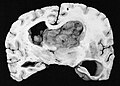

Subependymal giant cell astrocytoma

Diagnosis in short

Subependymal giant cell astrocytoma H&E stain.

Gross/radiology

• Well-demarcated.

• Often projecting into a ventricle.

• May be calcified

• Circumscribed tumour.